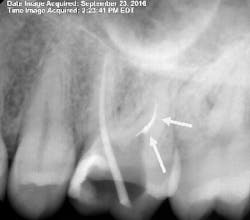

By 2:22 p.m., I was taking periapical x-rays with the gutta-percha to check my working lengths and evaluate the separated files. The x-ray showed that my access wasn’t as open as I originally thought it to be. The canal curved in two places, which caused the file separations. At this point I had two separated files—the 0.1 Twisted File (TF) file and the 15 mm hand file I had used to bypass the canal.

I proceeded to bypass the separated files with a 10 c-file. The apex locator still wasn’t giving me a reading. I was ready to obturate the canal, leaving all the extra metal as fill. Upon drying the canal with paper points, I noticed the paper point disappeared immediately toward the buccal. I took a step back to remove the buccal wall for better access. At this point, I was able to visualize the DB canal much better and was able to remove both of the separated instruments.

After obturation, it became apparent why the apex locator had given no reading for the DB canal. The foramen was located 3–4 mm away from the apex and on a curve that no file could reach. As a result of copious irrigation, the sealer was expressed from the apex.